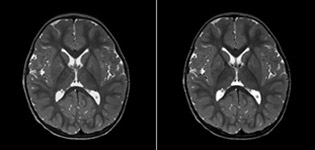

Routinemäßige homogene Fettsuppression unter praktisch allen Bedingungen mit mDIXON TSE

Philips mDIXON TSE ist ein Zweipunkt-DIXON-Verfahren, das Wasser- und Fettsignale trennt und so eine zeiteffiziente, fettfreie Bildgebung auch bei komplexen neurologischen Anatomien ermöglicht. „mDIXON TSE ist eine der signifikantesten Verbesserungen bei Bildgebungssequenzen, die wir am PCH bisher realisiert haben“, sagt Dr. Miller. „Dank der multiparametrischen Erfassung können wir Bilder mit Fettsuppression und entsprechende T2-Bilder ohne Fettsuppression in derselben Sequenz aufnehmen. Außerdem war es bei den bisherigen Methoden möglich, dass diese durch Artefakte aufgrund einer ungünstigen Patientenanatomie oder durch Bedienfehler beeinträchtigt wurden. Mit mDIXON verfügen wir jetzt jedoch über eine robuste und zuverlässige Methode zur Fettsuppression.“ Historisch gesehen bereitet die Fettsuppression am Ende des Sichtfeldes Schwierigkeiten, insbesondere bei der Bildgebung der gesamten Wirbelsäule und bei diffizilen Patientenanatomien wie dem unteren Halsbereich. „Aufgrund der einzigartigen Fettsuppressionseigenschaften von mDIXON treffen diese Probleme jedoch nicht mehr zu“, erläutert Dr. Miller. „Wir erhalten routinemäßig eine homogene Fettsuppression unter praktisch allen Bedingungen. Darüber hinaus konnten wir auch die Effizienz steigern, weil wir keine Sequenzen mehr aufgrund solcher technischen Einschränkungen wiederholen müssen.“

„mDIXON TSE hat unsere Diagnosesicherheit erhöht, weil Abweichungen, bei denen die Fettsuppression für die Diagnose entscheidend ist, definitiv abgeklärt werden können, zum Beispiel metastatische Erkrankungen oder ossale Veränderungen.“

„mDIXON TSE erweist sich bei Patienten mit Läsionen oder pathologischen Befunden im Weichteilgewebe wie Gesicht und Hals am nützlichsten sowie bei Patienten mit kontrastverstärkenden Abweichungen, die mit Fettsuppression am besten sichtbar sind“, so Dr. Miller weiter. „Unsere gesamte Wirbelsäulenbildgebung enthält mittlerweile mDIXON T2-Bilder auf reiner Wasserbasis, und dies ermöglicht uns die Erkennung von Pathologien, die bei einer Bildgebung ohne Fettsuppression zum Beispiel von Knochenverletzungen nicht sichtbar wären. Außerdem ist es nicht nötig, weitere TSE-T2-Standardbilder aufzunehmen, weil die mDIXON In-Phase-Bilder gleichwertig mit TSE-T2-Standardbildern sind.“